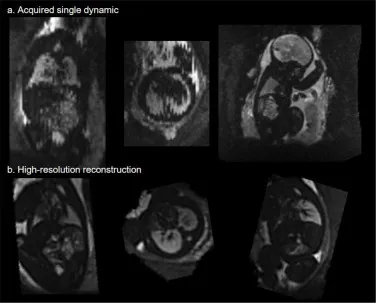

图4.上排(a):重建前单个有运动伪影的动态图像示例。请注意左侧和中间图像中可见的切片之间的运动伪影;下排(b):同一病例在所有三个平面上重建后的3D体积,运动伪影已消除。